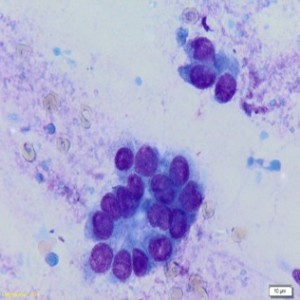

Citodijagnostika je skupina morfoloških, minimalno invazivnih, neagresivnih pretraga koje se primjenjuju odmah u početku dijagnostičkog postupka. Mogu se ponavljati jer ne ostavljaju nikakve trajne posljedice na analiziranom tkivu ili organu.

Aspiracijska citologija izvodi se tankom iglom najčešće pod kontrolom ultrazvuka, a dobiveni materijal u vidu razmaza biva nanesen na stakalce, osušen na zraku i obojan May-Grünwald-Giemsa metodom.

Prednosti citološke punkcije leže u činjenici da se radi o kratkotrajnom ambulantnom zahvatu za koji nije potrebna lokalna anestezija, primjena je povezana s malom učestalošću komplikacija, a rezultati su pouzdani i vrlo brzo dostupni.

Aspiracijska citologija dojke rabi se kao prva dijagnostička metoda nakon čega slijedi patohistološka verifikacija nejasnih, suspektnih i svih malignih dijagnoza. Materijal za patohistološku analizu može se dobiti biopsijom širokom iglom i kirurškom biopsijom.